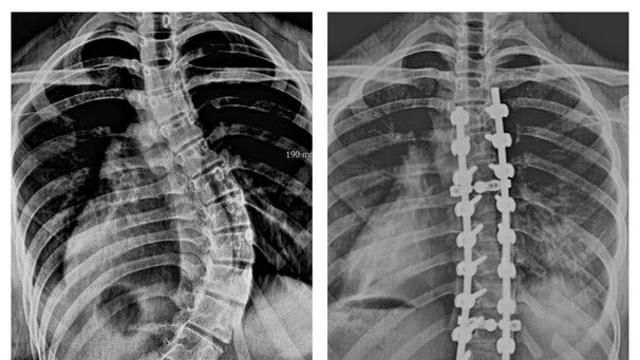

척추 65도 휜 13세 여학생 희망 찾아… 국제바로병원, 고도굴곡 척추측만증 수술 성공

최근 고도굴곡 척추측만증 수술을 받은 A양(13)의 X-Ray 사진. 왼쪽은 척추가 65도